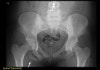

X-ray에서 견열 골절(avulsion fx)이 있는 부위를 찾을 수 있습니다.

X-ray : 골반 견열골절(Pelvic avulsion fracture, crest)

X-ray : 골반 견열골절(Pelvic avulsion fracture, ASIS)

X-ray : 골반 견열골절(Pelvic avulsion fracture, AIIS)

X-ray : 골반 견열골절(Pelvic avulsion fracture, ischial tuberosity)